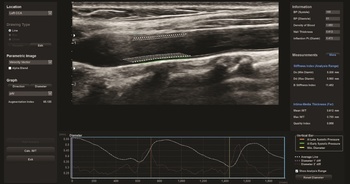

A sugárterheléssel nem járó ultrahangvizsgálatokat számos területen alkalmazzák az ikerkutatásban (1. és 2. a, b ábra), a policisztás ovárium szindrómától kezdve a szaruhártya megítélésén át az érelmeszesedés vizsgálatáig széleskörűen alkalmazott módszer. Néhány ultrahangos ikervizsgálatot emelnénk ki ezek közül. A finn ikerregiszter hüvelyi ultrahang vizsgálattal ítélte meg a méh gyakori jóindulatú daganata, a mióma előfordulását. A miómák száma gyenge genetikai meghatározottságot igazolt, míg a miómák előfordulása összefüggést mutatott a magasabb testsúly-testmagasság indexszel (Luoto et al., 2000). A fejlődő országokban egyre gyakrabban előforduló epekövesség molekuláris patogenezise nem teljesen ismert. A svéd ikerregiszter munkatársai epekövességben szenvedő ikerpárok – részben ultrahangos – vizsgálata során kimutatták, hogy az ABCG8 D19H génvariánst hordozó egyéneknek nagyobb az epekövességre való hajlamuk (Katsika et al., 2010). A hazánkban is minden negyedik felnőttet érintő nem alkoholos zsírmáj hátterében additív genetikai hátteret nem igazolt vizsgálatunk, közös (74,2%) és egyéni (25,8%) környezeti tényezők állnak a betegség hátterében (Tárnoki et al., 2012). Szintén hazai ikermintánkon ultrahanggal vizsgáltuk a veseparenchima vastagságában szerepet játszó genetikai meghatározottság mértékét, mely korra és nemre korrigálva 0%-os volt, a közös (30%) és egyéni (70%) környezeti tényezők hatásai domináltak. Eredményeink az életmód, illetve a primer prevenció fontosságára hívták fel a figyelmet (Tárnoki et al., 2013).

2. a, b ábra. Egypetéjű magyar ikerpár két tagjának (A: elsőszülött, B: másodszülött) arteria carotis communis automatikus IMT mérése (disztális falon avektorral jelölt terület alatt), illetve localis stiffness mérése

A

B